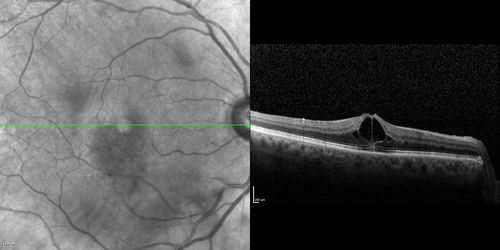

Branch Retinal Vein Occlusion with worse macular edema from hypertension - SD-OCT shows Edema Right Eye

BRVO Old Increased Edema with Hypertension - Improved with lower Blood Pressure